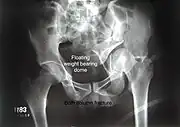

Both column fracture showing floating weight bearing dome